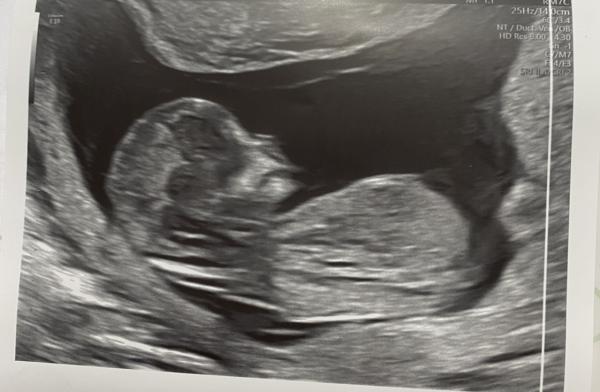

Hey ihr,  Ich hatte gestern mein ETS bei 13+1. Kennt sich jemand mit der Nub Theorie aus und kann eine Tendenz fürs Geschlecht abgeben? Ich würde mich total über eure Meinung freuen.

Bild zu Junge oder Mädchen, kann jemand helfen? - Schwanger - wer noch? Rund um die Schwangerschaft

Guten Morgen Mama19.21,  leider ist auf deinen Bildern der Nub nicht mit drauf. Drücke dir aber die Daumen, dass die Zeit schnell vergeht und ihr bald wisst, was es ist 🥰 Liebe Grüße